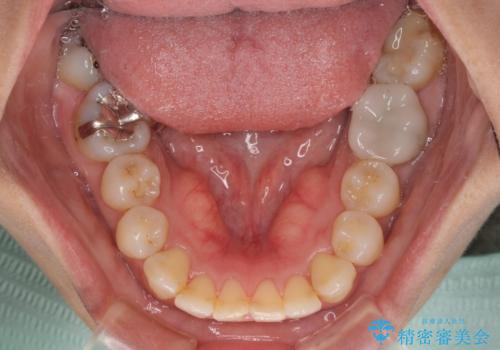

【モニター】処置歯の多い歯列 インビザラインでデコボコを整える

- 上下前歯のデコボコを気にして来院された患者様です。

歯列としては、ワイヤー装置でもインビザラインでも、どちらでも対応可能でしたが、処置されている歯が多く、ワイヤー装置を装着するためには処置歯のやり直しが必要な状態でした。

インビザラインでもアタッチメントを装着できないという同様のデメリットがありますが、比較的矯正治療を行いやすい歯列であったので、インビザラインによる矯正治療を行うこととしました。